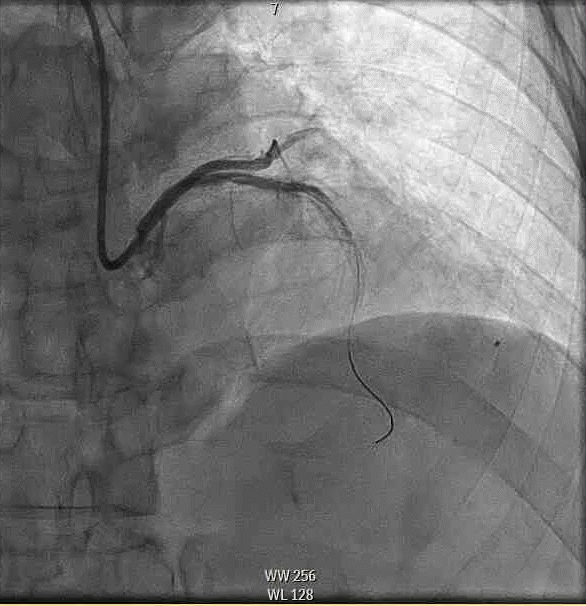

A woman in her late 60s with a history of coronary artery disease presented for proximal left anterior descending PCI in the setting of a non-ST-elevation myocardial infarction (Figure 1A). The procedure was complicated by a distal coronary artery perforation caused by a coronary wire (Figure 1B, Video 1). The patient remained hemodynamically stable.

Figure 1. Initial angiography with severe stenosis of the proximal left anterior descending (blue arrow) (A). After intervention, a coronary artery perforation is seen in the distal vessel (blue arrow) (B). Transthoracic echocardiography showing the left ventricle and right ventricle (C). CEE after intracoronary injection of the UEA, the UEA is seen filling the right ventricle while notably absent from the pericardium (D).